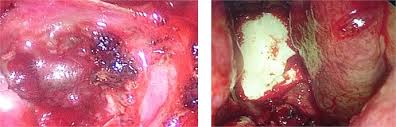

Hình 6. Lấy u